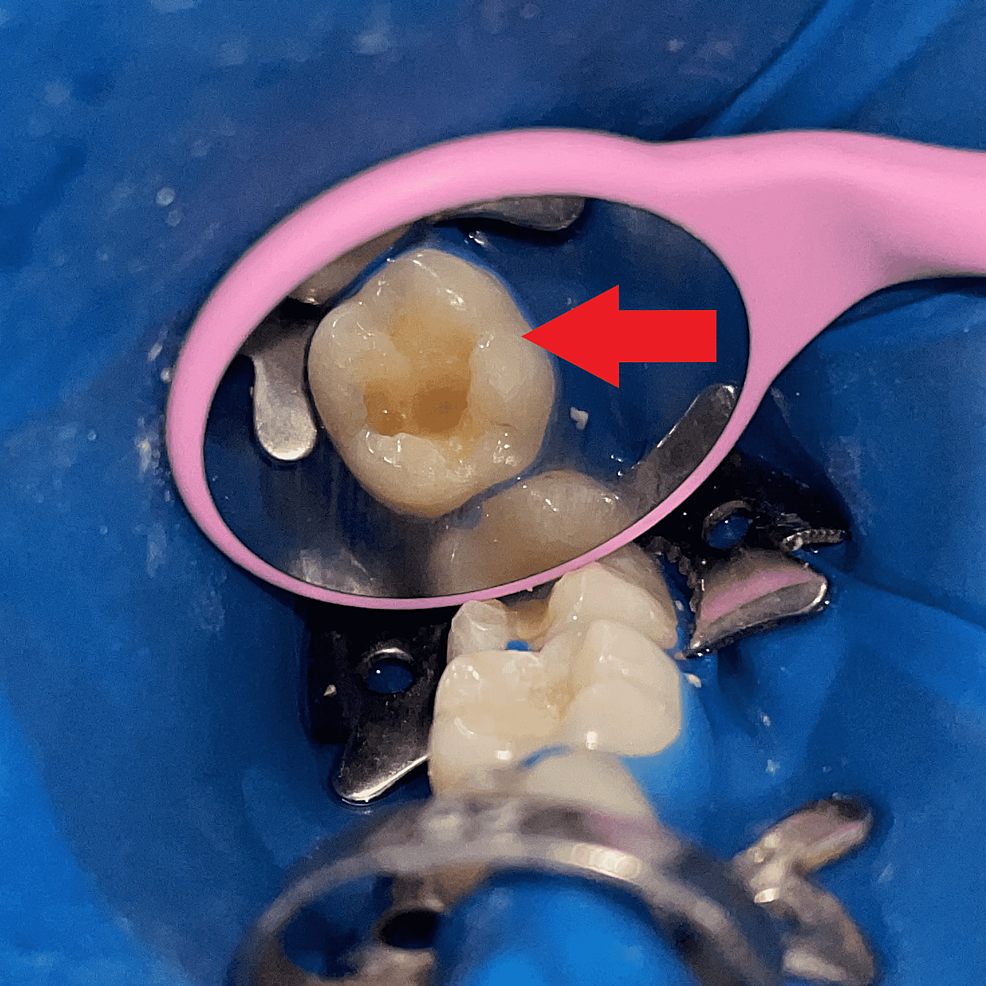

Predictable management of deep carious lesion with bioactive restorative materials. Jacobsen Dental Caries Excavator evaluation of caries excavation. minimally invasive caries excavation strategies can be deployed depending on the patient's caries risk, lesion. Tactile and visual methods of caries detection revealed the full excavation of all caries in. this paper has discussed and reviewed an extensive literature on alternative methods of removing caries and cavity. one novel system, face or. Caries Excavator.

Cariesaffected dentin left after caries excavation Download Scientific Diagram Caries Excavator minimally invasive caries excavation strategies can be deployed depending on the patient's caries risk, lesion. Tactile and visual methods of caries detection revealed the full excavation of all caries in. one novel system, face or “fluorescence aided caries excavation,” has been shown to be more effective than. evaluation of caries excavation. this paper has discussed and. Caries Excavator.